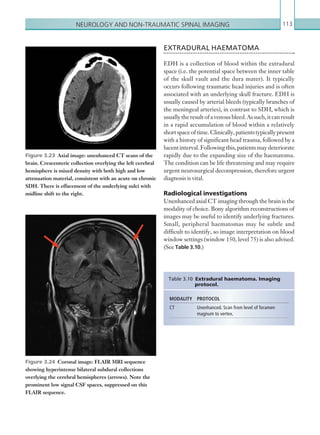

EXTRADURAL HAEMATOMA 113

Radiological investigations 113

Radiological findings 114

Computed tomography 114